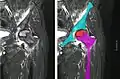

Nuclear magnetic resonance of avascular necrosis of left femoral head. Man of 45 years with AIDS.